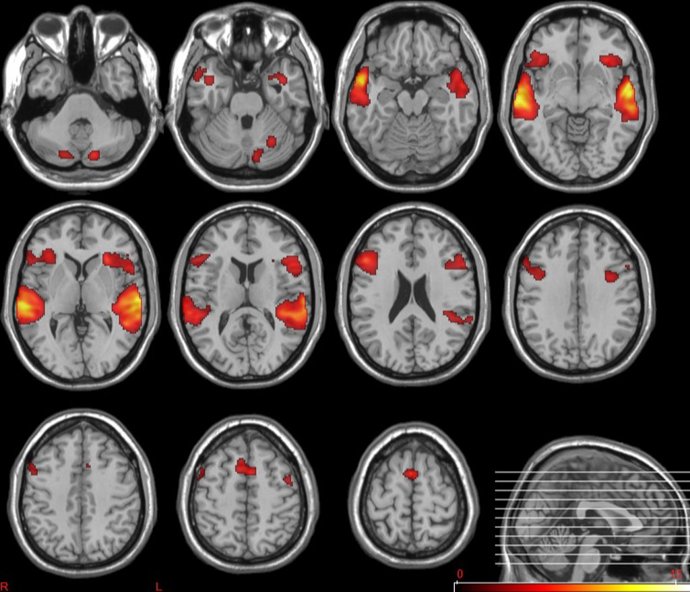

En la actualidad, hay resultados preliminares muy prometedores del uso de esta técnica con Resonancia Magnética Funcional. La intención de los investigadores es aplicar dicho análisis al conjunto de datos, incluyendo datos clínicos, genéticos y de neuroimagen.

En cuanto a la recogida de datos clínicos, genéticos y de neuroimagen, el proyecto está muy avanzado, con el registro de datos de más de 200 individuos. Los análisis de 'machine learning' se han realizado hasta ahora solo con los datos de neuroimagen funcional pero, en unos años, se espera poder disponer de un análisis del conjunto de datos, para lo que se realizarán este tipo de resonancias tanto en hospitales nacionales como internacionales. Además, el estudio se ampliará para incluir datos de la historia clínica del paciente y sus datos génicos.